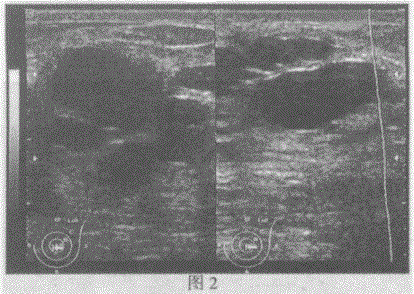

问题 临床资料:女,42岁,自诉停止哺乳2个月,左乳房疼痛伴肿大1周。 临床物理检查:左乳明显增大,乳头半凹,局部轻度水肿。触诊外下象限可扪及一肿物,边界不清,质硬,压痛明显,无波动感。 超声综合描述:左乳腺腺体层厚度2.6cm,明显增厚,结构紊乱,回声明显不均,外下象限可见5.2cm×3.3cm不均质回声区(图1),边界欠清,内可见增强回声,探头加压后局部压痛明显;左乳头外侧可探及大小不等形态各异无回声(图2),CDFI:左乳腺腺体层内血流信号较右侧增加。 超声提示: